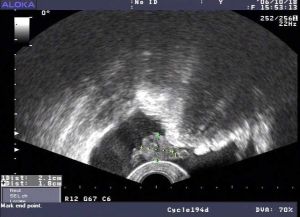

檢查

盆腔積水檢查對識別來自輸卵管、卵巢及腸管粘連形成的包塊或膿腫有85%的準確性。一般用來診斷較為嚴重的盆腔炎。

盆腔積水可詳細結合病史、症狀以及體症等明確是正常積液還是異常積液。如確診為異常積液則要明確導致積液的原因,病因性診斷是關鍵。

抽取積液是明確診斷的主要手段,適用於有性生活的婦女。